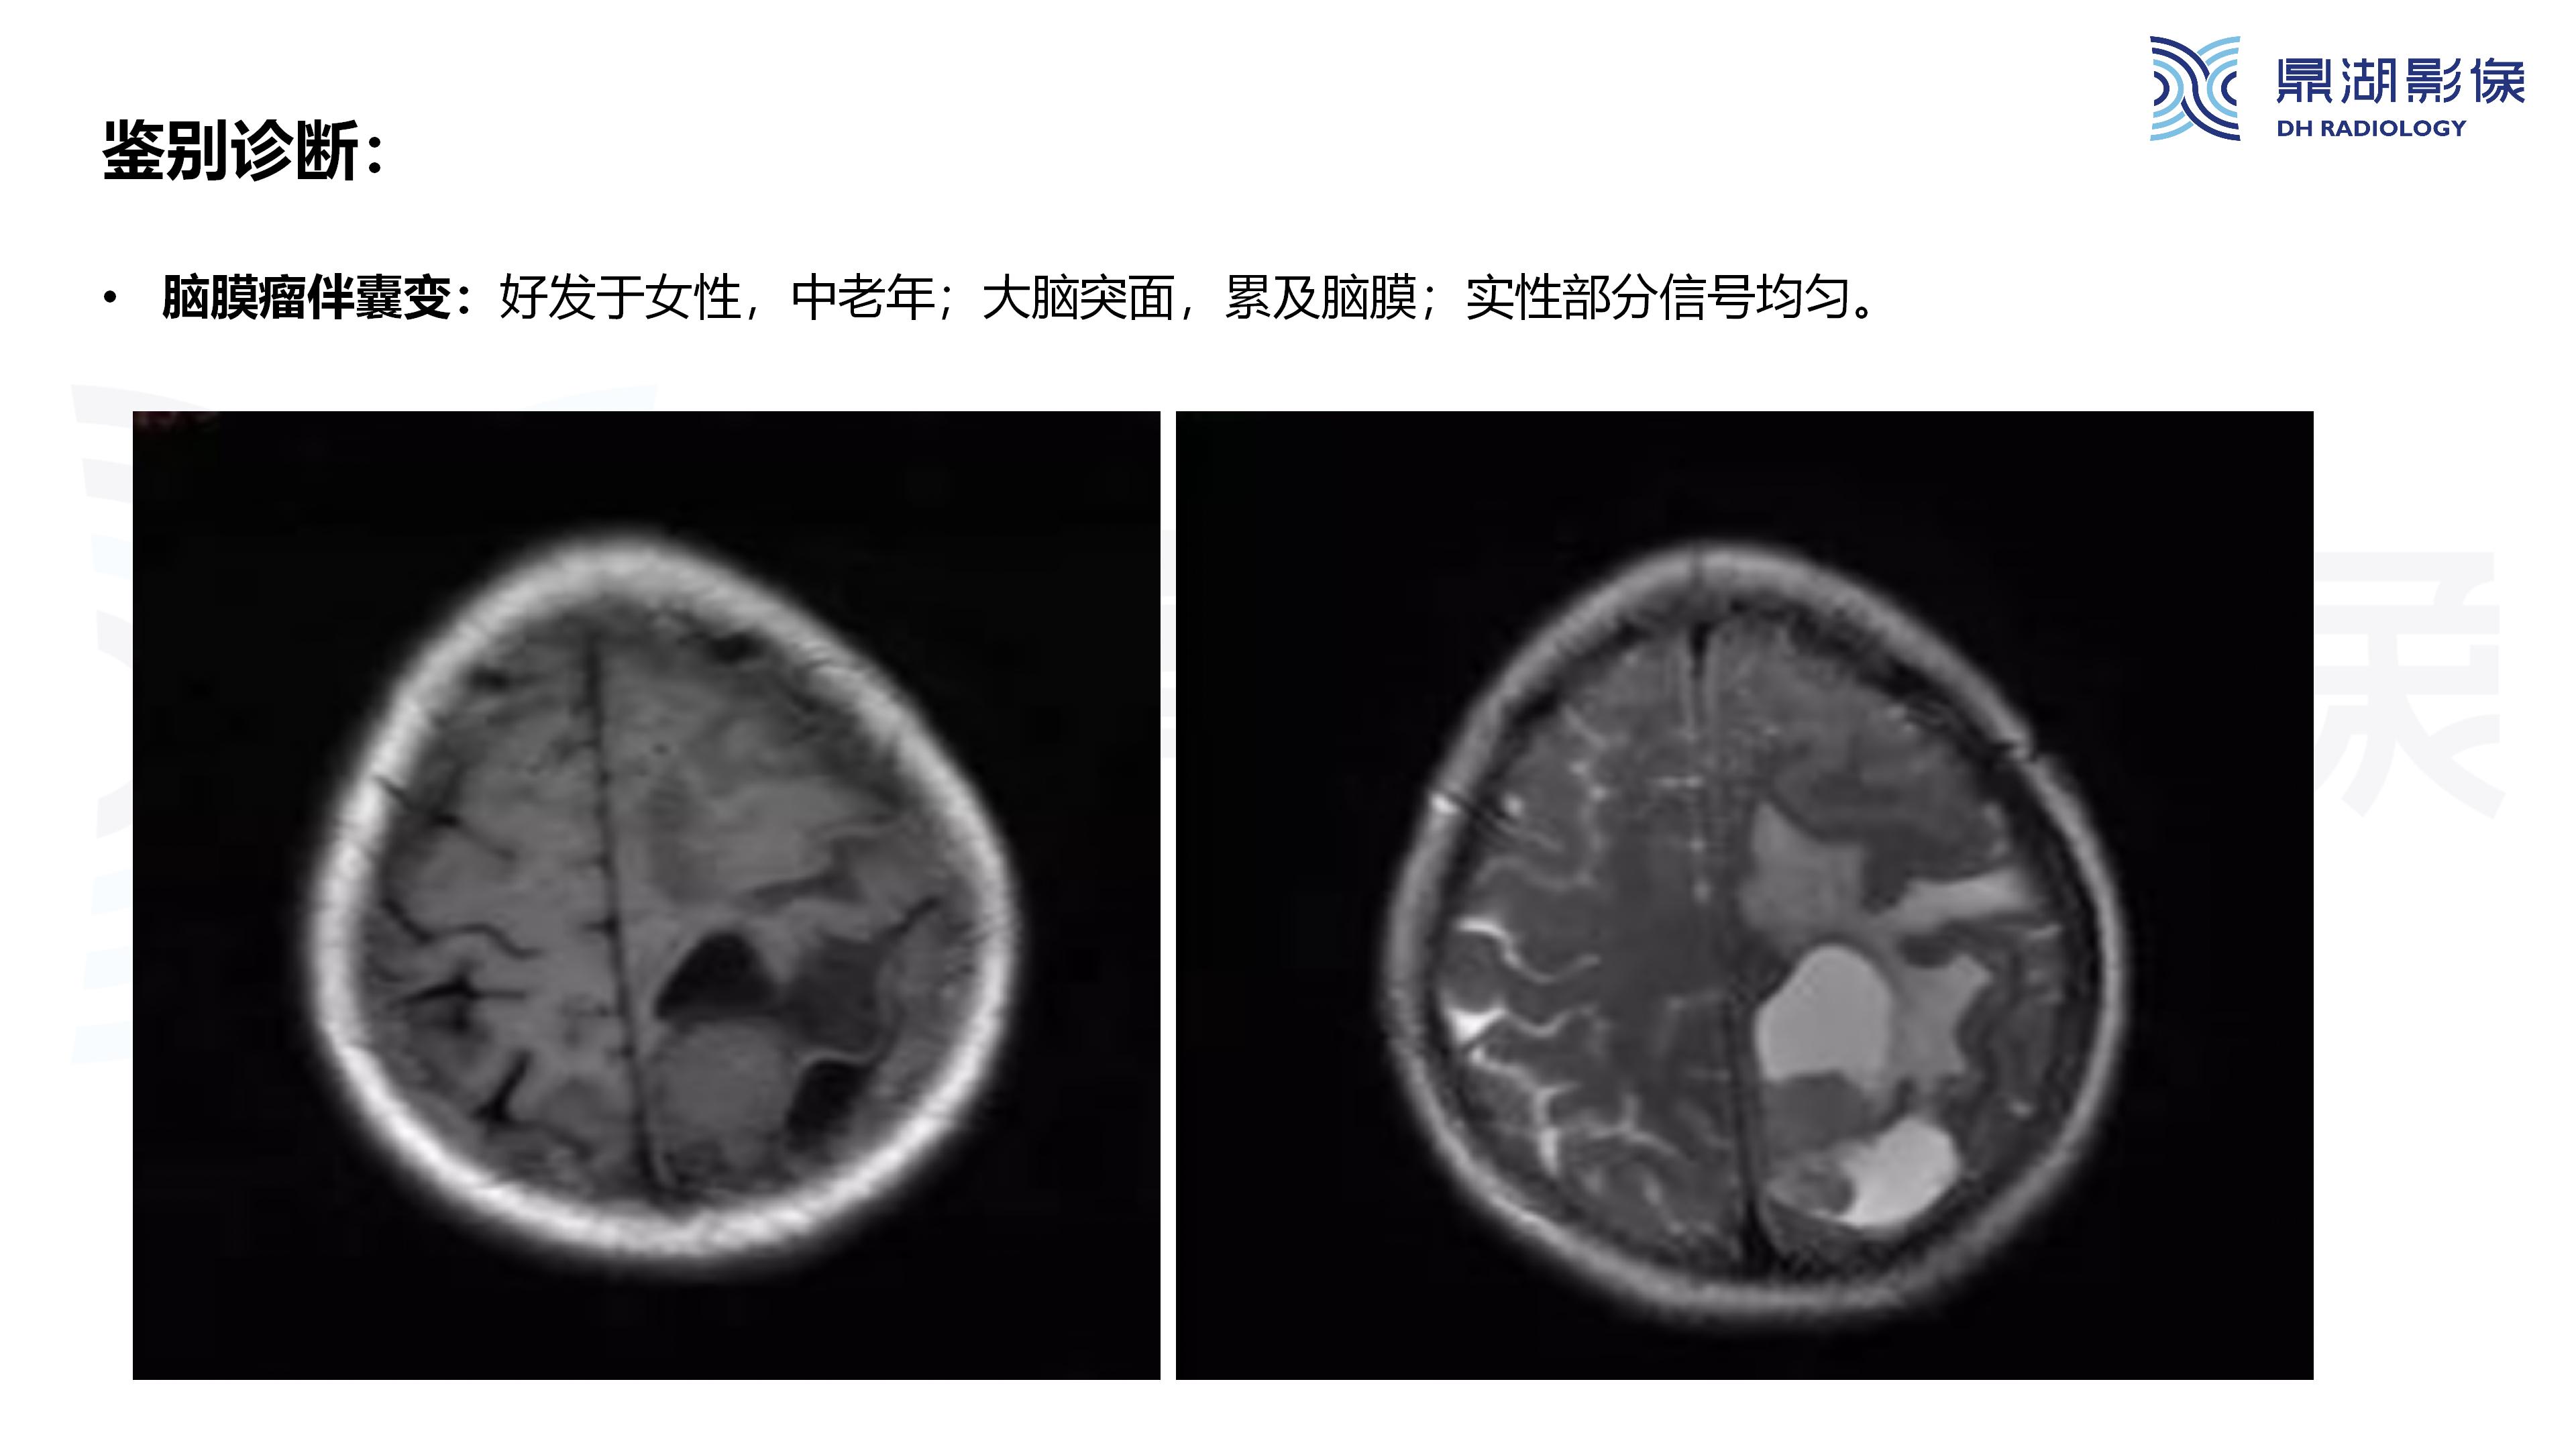

病例分析